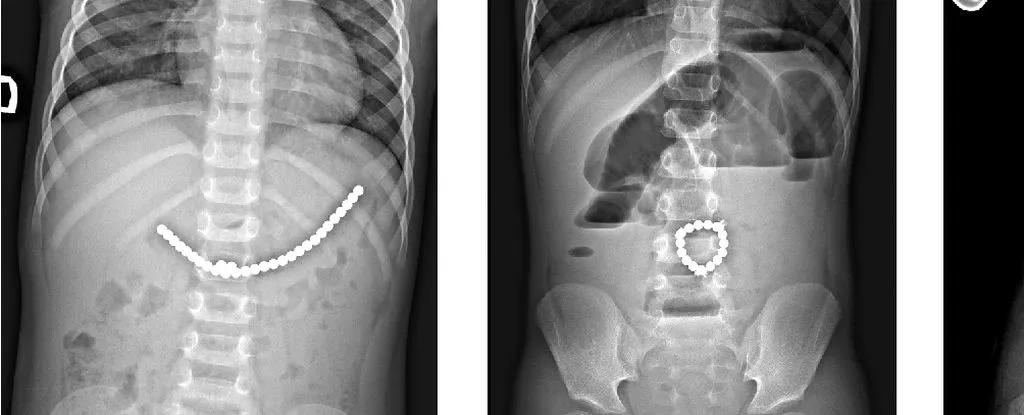

手术取出的磁铁链来源:Lekamalage et al.,NZMJ,2025

儿童吞食小型磁珠后的 X光片。来源:Daškevičiūtė et al.,2017